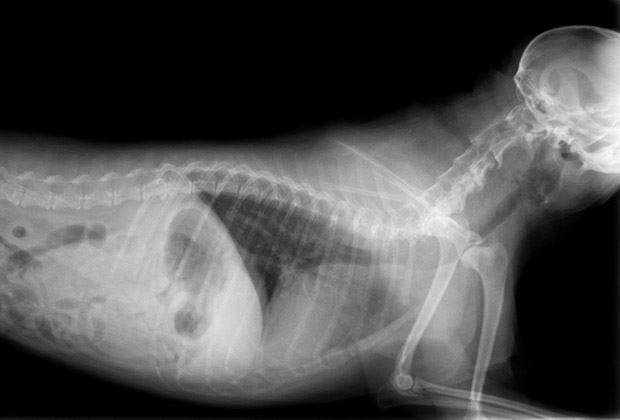

Die Luzerner Hirslanden-Klinik St. Anna untersucht nicht nur Menschen radiologisch - nach Betriebsschluss liegen auch Kleintiere auf dem Untersuchungstisch. Das Privatspital rechtfertigt das eher ungewöhnliche Angebot mit der entsprechenden Nachfrage.

Es treffe zu, dass in der Klinik St. Anna aufgrund von Anfragen von Tierärzten aus der Region Luzern Kleintiere in bestimmten Fällen radiologisch untersucht würden, erklärte Claude Kaufmann, Sprecher der Hirslanden AG, auf Anfrage der sda. Er bestätigte entsprechende Recherchen der «SonntagsZeitung».

Laut dem Sprecher fehlt in der Region Luzern bisher ein vergleichbares diagnostisches Angebot. Das Spital untersucht etwa Lawinen- oder Katastrophenschutzhunde, die aufgrund von akuten Lähmungserscheinungen schnell einer bildgebenden Diagnostik zugeführt werden müssen. Die Klinik nehme keine Eingriffe oder invasive Verfahren vor - es handle sich ausschliesslich um Untersuchungen mit MRI-Geräten.

Der Klinik-Sprecher hält fest, dass die Untersuchungen nach Betriebsschluss stattfinden, um die strikte Trennung zu den tagsüber stattfindenden Patientenströmen in der Klinik einzuhalten. Die Klinik befolge dabei spezielle Hygiene-Prozesse, deren Einhaltung zwingend kontrolliert werde.

Die Kosten für die Untersuchungen betragen zwischen 600 und 1000 Franken. Dabei entfalle nur ein Teil der Kosten auf die technische, bildgebende Leistung der Klinik, so Kaufmann. Ein anderer Teil entfalle auf ärztliche Interpretation der Befunde durch die medizinischen Fachspezialisten. Die Klinik St. Anna stelle die daraus resultierenden Einnahmen transparent dar und weise diese in Form einer offiziellen Klinikrechnung aus, hält Kaufmann fest: «Krankenkassen werden dadurch in keiner Weise belastet.»